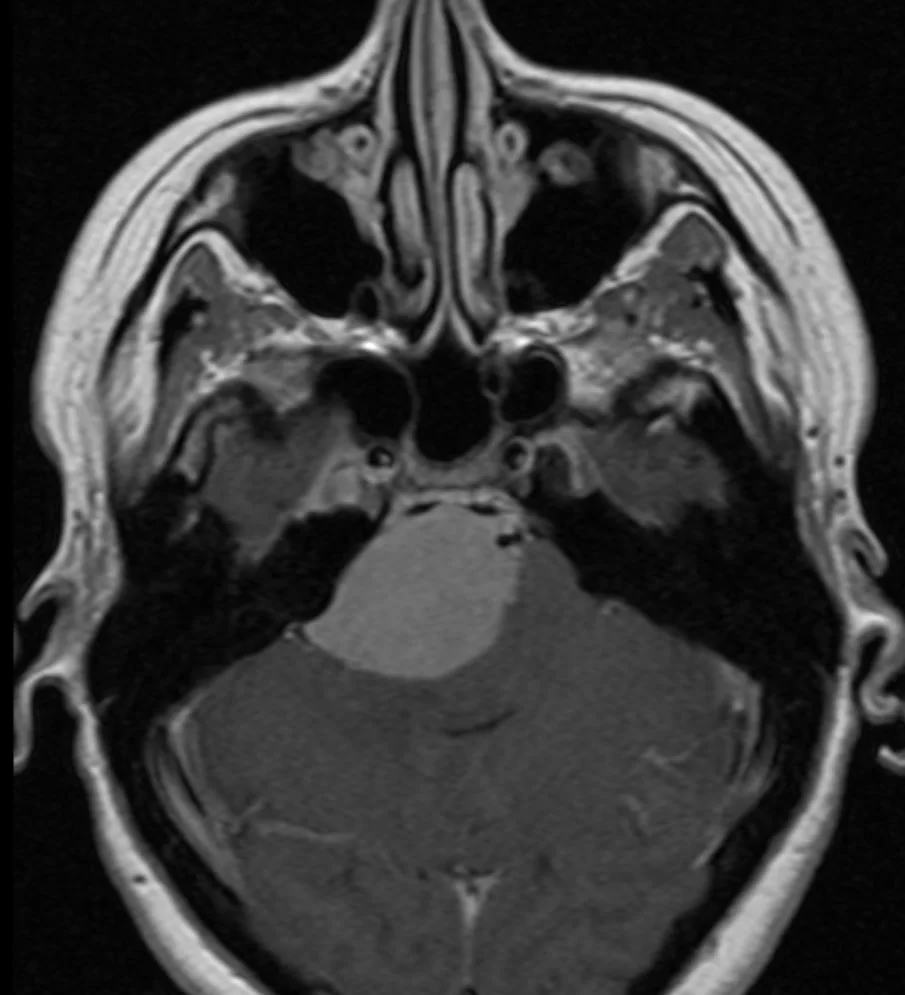

Ευμεγεθες Ακουστικό Νευρίνωμα με πίεση επί του εγκεφαλικού στελέχους

Ασθενής άνδρας, 48 ετών με συμπτώματα εμέτου και αδυναμίας από 15ημέρου περίπου. Στην αντικειμενική εξέταση διαπιστώθηκε σημαντική πάρεση προσωπικού νεύρου αριστερά και αστάθεια βάδισης &